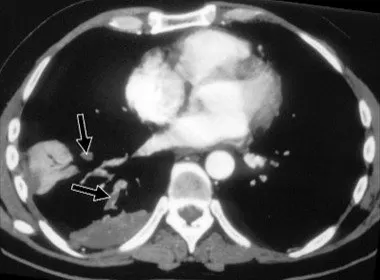

EMBOLIA GASSOSA ARTERIOSA (E.G.A.)

Patogenesi in ambito subacqueo

Sovradistensione polmonare da risalita veloce (barotrauma);

Pervietà misconosciuta del setto interatriale;